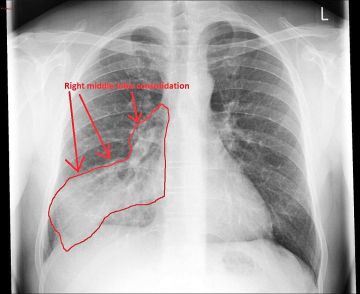

وأوضح النمر أن زيت الزيتون يمكن أن يتسرب إلى الرئتين مع التكرار، مما يسبب نوعًا من الالتهاب الرئوي يُعرف طبيًا باسم Pneumonitis Lipoid، وهو التهاب دهني يظهر بأعراض مثل الكحة، ضيق التنفس، وارتفاع الحرارة، وتُظهر الأشعة علامات واضحة لهذا الالتهاب.